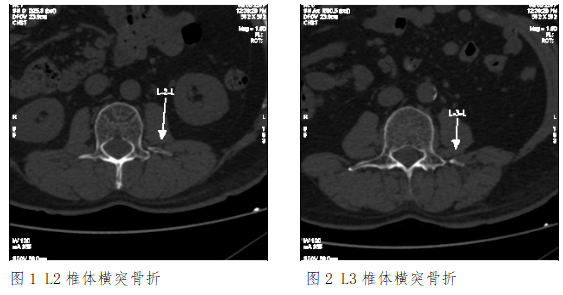

辅查:XXX医院CT示:L2、L3左侧横突骨折。

诊断:L2、L3左侧横突骨折。

XXX医院CT(2017-7-3)示:L2、L3左侧横突骨折,断端骨皮质局部连续,断端圆钝、硬化,提示陈旧性骨折。

根据检验所见赖XXL2、L3左侧横突骨折,断端骨皮质局部连续,断端圆钝、硬化,结合案情分析认为,赖XX腰2、3椎体左侧横突骨折系本次外伤前即存在的陈旧性骨折,且骨折时间较长,与本次外伤无直接因果关系,不宜据此进行损伤程度鉴定。横突新鲜性和陈旧性骨折在CT片上的区别主要根据断端形态,一般横突新鲜性骨折,断端锐利,骨折线清晰,而横突陈旧性骨折一般断端有愈合,若分离较大至骨不连,断端会呈现圆钝、硬化改变。